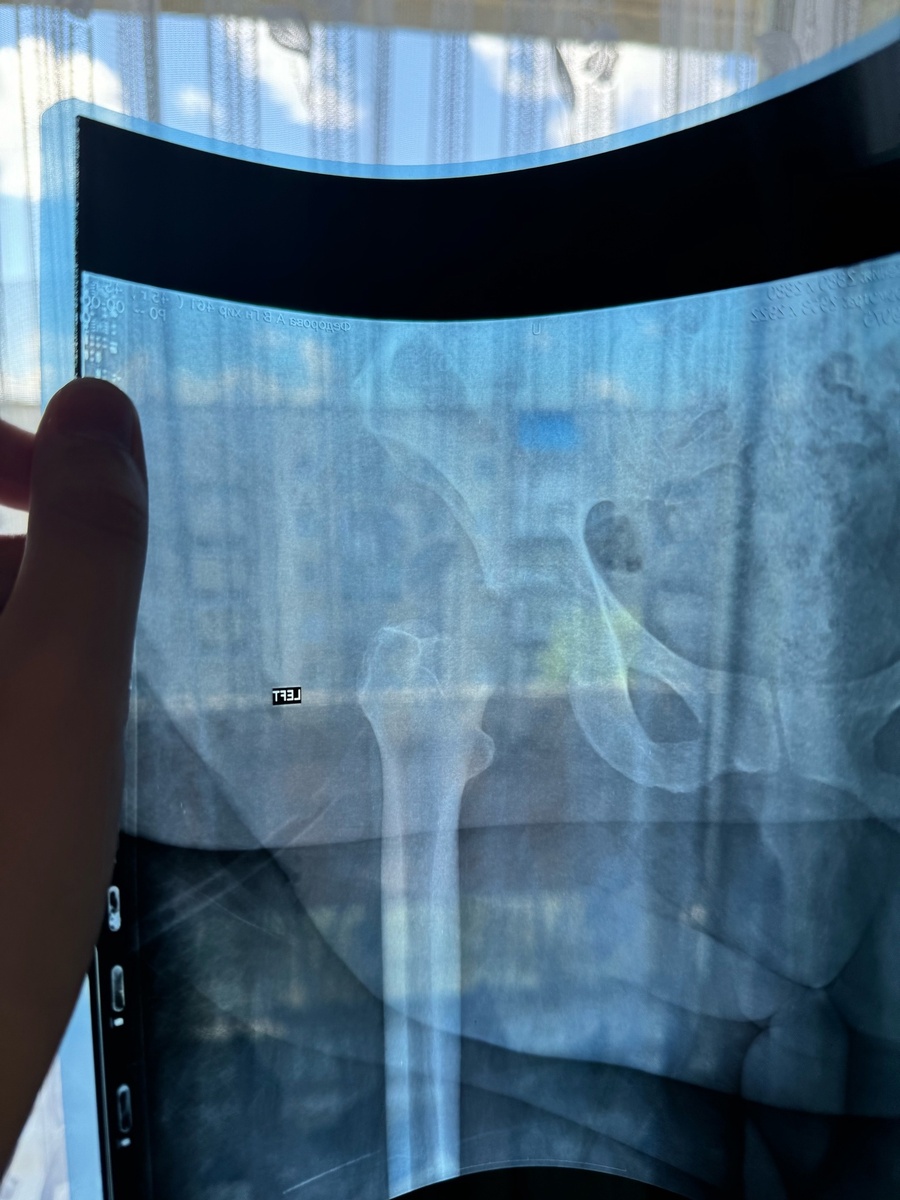

В один из вечеров я спала, и во сне повернулась на бок, почувствовала сильнейшую боль в ноге и потеряла сознание. Придя в себя, дома уже была бригада неотложки, упаковывала меня в деревянный корсет ( я не знаю, как точно называется это приспособление), предполагая перелом. Стоило мне чуток двинуть ногой, я тут же теряла от боли сознание. Увезли в дежурную травматологию , сделали снимки, и опять ничего не нашли. Поставили обезболивающий укол и отправили в поликлинику по месту жительства выяснять причину моего состояния. По прежнему никаких признаков моего недуга понять не могли. Ни простуды, ни сыпи, ни покраснений на теле не было. Только с этого момента дикая боль в ноге не дала мне хоть как то передвигаться и даже лишила меня сна. Я выла от боли круглосуточно. Описать боль даже невозможно. Находилась в постоянном бреду, осознанное состояние приходило редко.

Видя моё состояние, терапевт приняла решение отправить меня на срочную госпитализацию, т.к. у меня нарушились многие показатели анализов и падал гемоглобин. Скорая доставила меня в дежурный стационар, и после некоторых обследований, через час, я оказалась на операционном столе. Был абцесс тазобедренного сустава, остеомиелит и распространился в мягкие ткани бедра. После того, как мне ввели наркоз в позвоночник, я почувствовала облегчение, впервые за долгий промежуток времени. От слабости я начала засыпать, но врачи не давали, что то спрашивали помню, но по большей степени переговаривались между собой. Но даже на тот момент, я не понимала всю серьёзность моего положения. Только через некоторое время, мне сказали, что меня в буквальном смысле, спасли... Я очень сложный пациент, с большим весом, диабетом, и критично был низкий гемоглобин. Меня спасли...Чему сейчас я очень рада.

Не буду описывать нюансы про пелёнки, судна, и оборудования моего лежачего пространства. Терапевт всё объяснила, как действовать дальше ( большое ей , и всем хирургам спасибо). Оформили инвалидность ( теперь у меня нет сустава). Многие вопросы еще не решены по средствам реабилитации. Но всё же я дома, и теперь у меня ничего не болит. Начались будни восстановления. Потихоньку научилась двигать ногой и тазом, переворачиваться на бока и живот. Каждый день занимаюсь зарядкой. Восстанавливаются показатели анализов и моральное состояние. Огромная благодарность семье, которые меня очень поддерживают. Радуются всем моим достижениям . Как маленький ребёнок, я снова учусь двигаться. Научилась пересаживаться в инвалидную коляску ( пока еще с помощью). Радуюсь, что могу сама доехать и посмотреть, пока, хотя бы в окно. В быту ещё мало, что получается, но я стараюсь. Не скрою, что была и депрессия и слёзы от настоящего положения. Моральная сторона никак не хотела осознавать реальность инвалидности. Когда невозможно сделать элементарных дел.